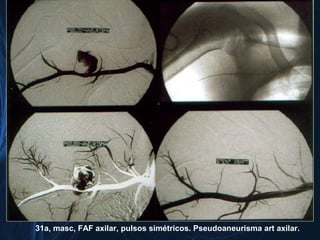

31a, masc, FAF axilar, pulsos simétricos. Pseudoaneurisma art axilar.

31a, masc, FAFaxilar, pulsos simétricos. Pseudoaneurisma art axilar.